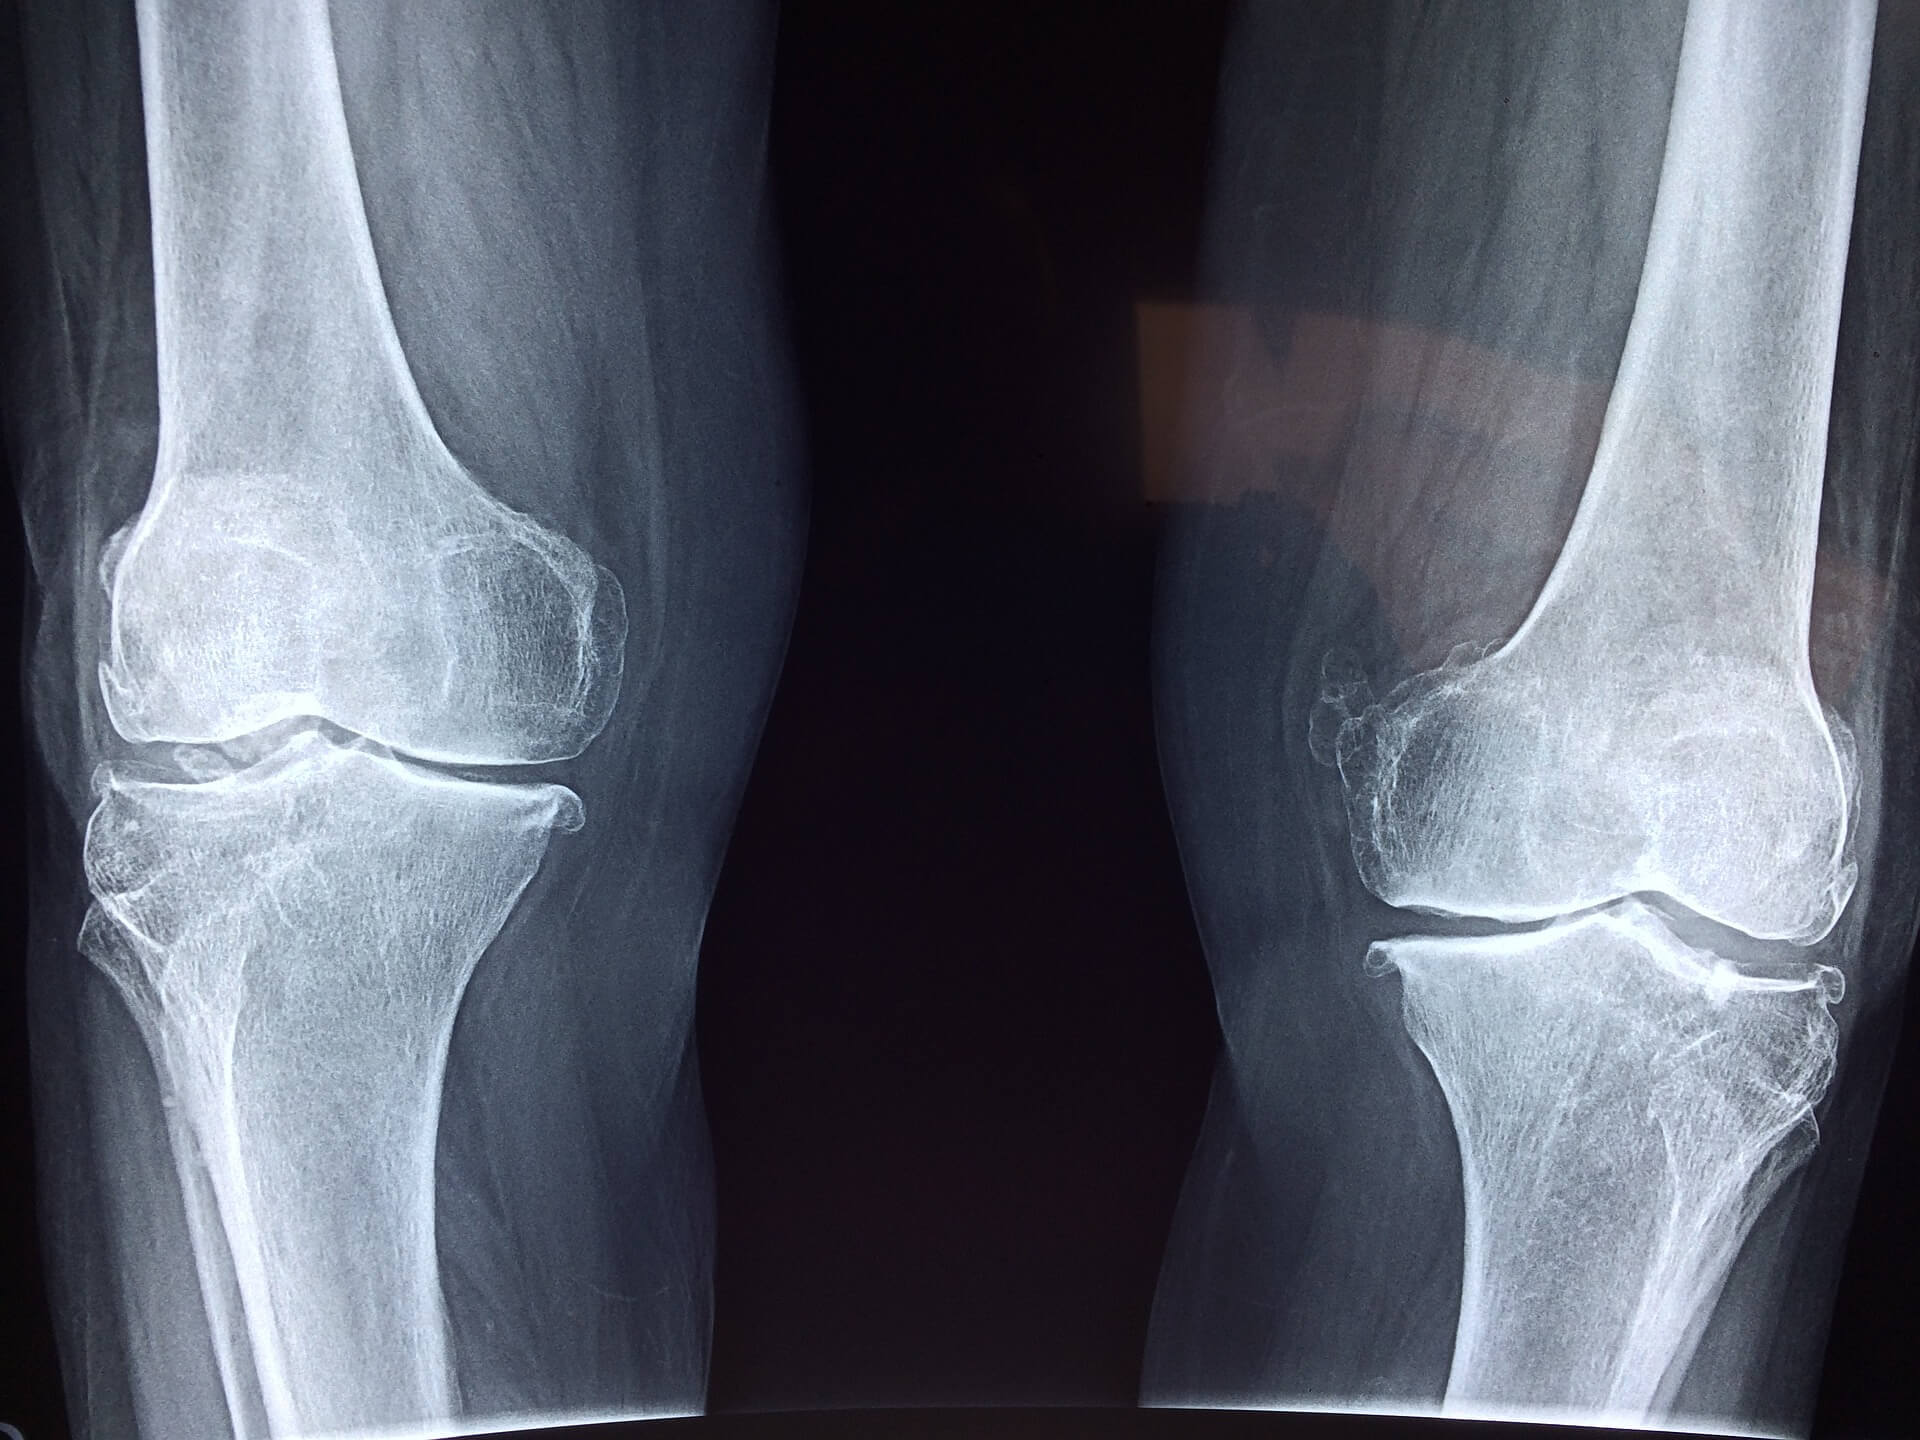

골관절염은 주로 성인의 관절 가동성에 영향을 미치는 질환으로, 관절 연골, 세포 외 기질, 연골하골의 점진적인 퇴화가 발생하는 것입니다. 이 같이 복잡해 보이는 골관절염의 증상은 삶의 질을 아주 많이 떨어뜨릴 수 있는데요.

이러한 골관절염은 천천히 점진적으로 진행되는 질환이며, 가장 흔한 증상은 통증, 부기, 경직, 활액막염, 변형, 관절 잡음입니다.

무릎 골관절염의 치료는 모든 사람의 증상의 강도에 따라 달라지며 약물이나 심지어 수술이 필요할 수도 있다고 합니다. 어쨌든, 약물치료는 확실히 대부분 증상을 완화할 수 있습니다.